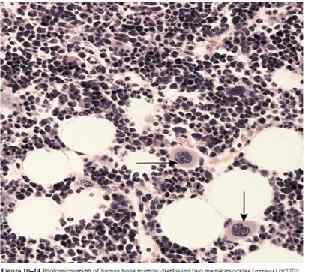

Красный костный мозг морской свинки. 1 - губчатое вещество кости; 2 - красный костный мозг; 3 - клетки миелоидного ряда; 4 - мегакариоцит; 5 - синусоидный кровеносный капилляр; 6 - артерия; 7 - жировая клетка.